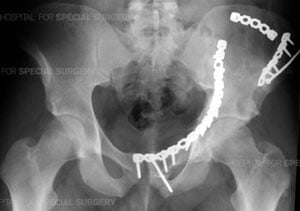

Radiograph of the pelvis following open reduction and internal fixation (ORIF) of a complex comminuted

fracture of the left acetabulum, hemipelvis and pubic symphysis.